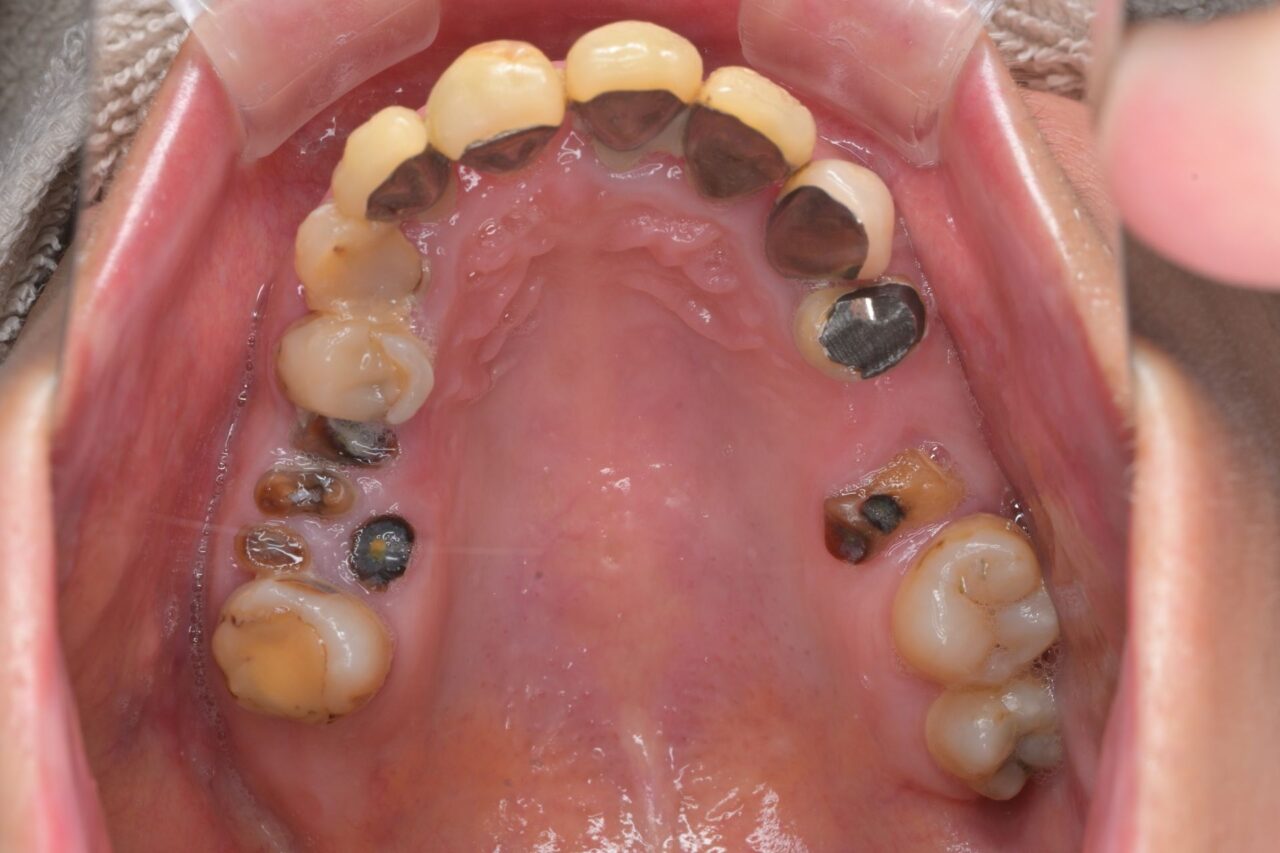

上面

大きな虫歯が放置されていた入り、かぶせ物が無くなって放置されていたり、様々な問題があります。保険治療で済ませようと思うと入れ歯は確定です。